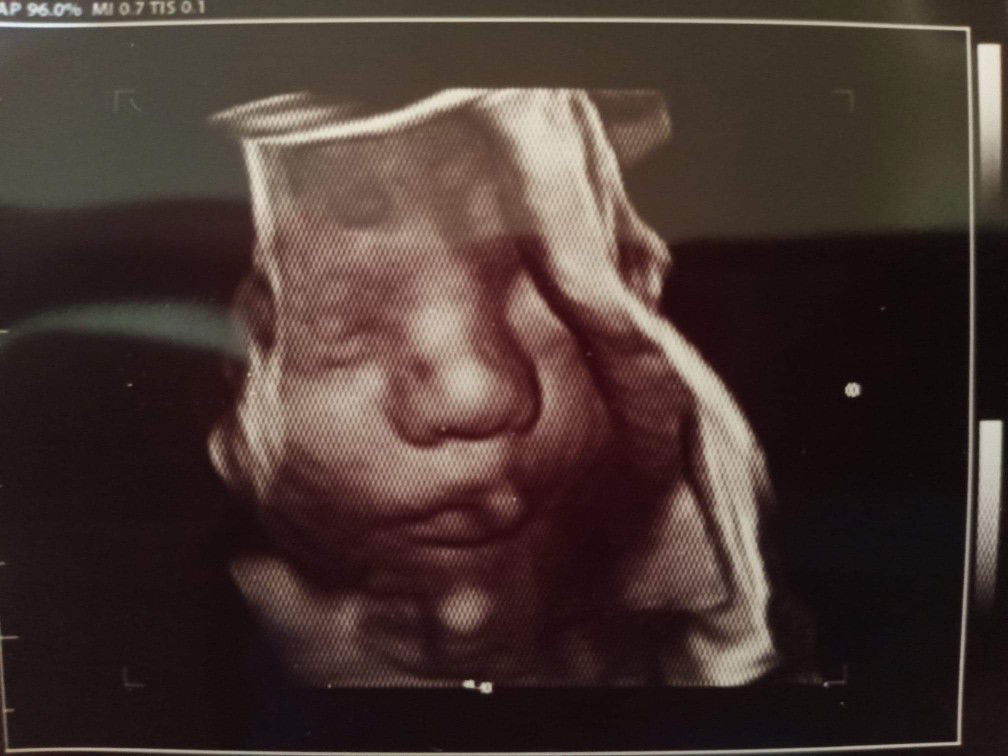

4D Ultrasound

My Baby boy.